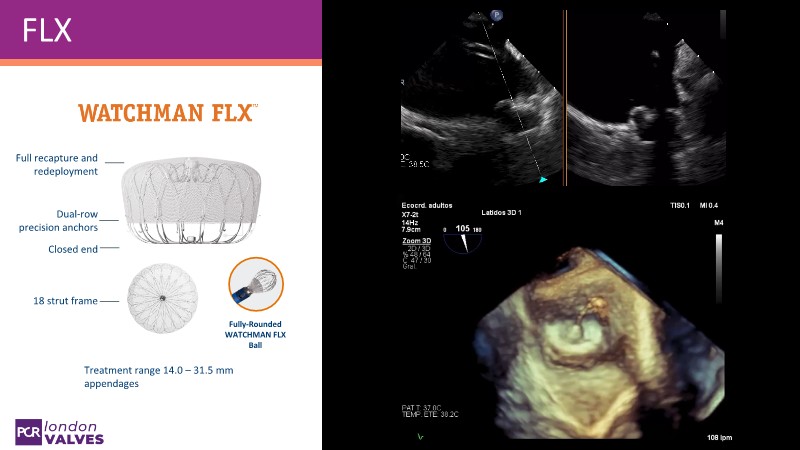

Explore the forefront of left atrial appendage (LAA) closure with this session focusing on the latest innovations and clinical opportunities. Topics include recent data on WATCHMAN FLX PRO and VersaCross Connect systems, workflow strategies to improve procedural efficiency, and discussions on upcoming clinical trials such as CHAF and LAAOS IV, emphasizing expanding stroke prevention options beyond bleeding risk reduction.

- To review the latest data on WATCHMAN FLX PRO and VersaCross Connect - HEAL LAA and subanalysis

- To learn workflow strategies to improve efficiencies for LAA closure - VersaCross Connect + PRO + TruSteer